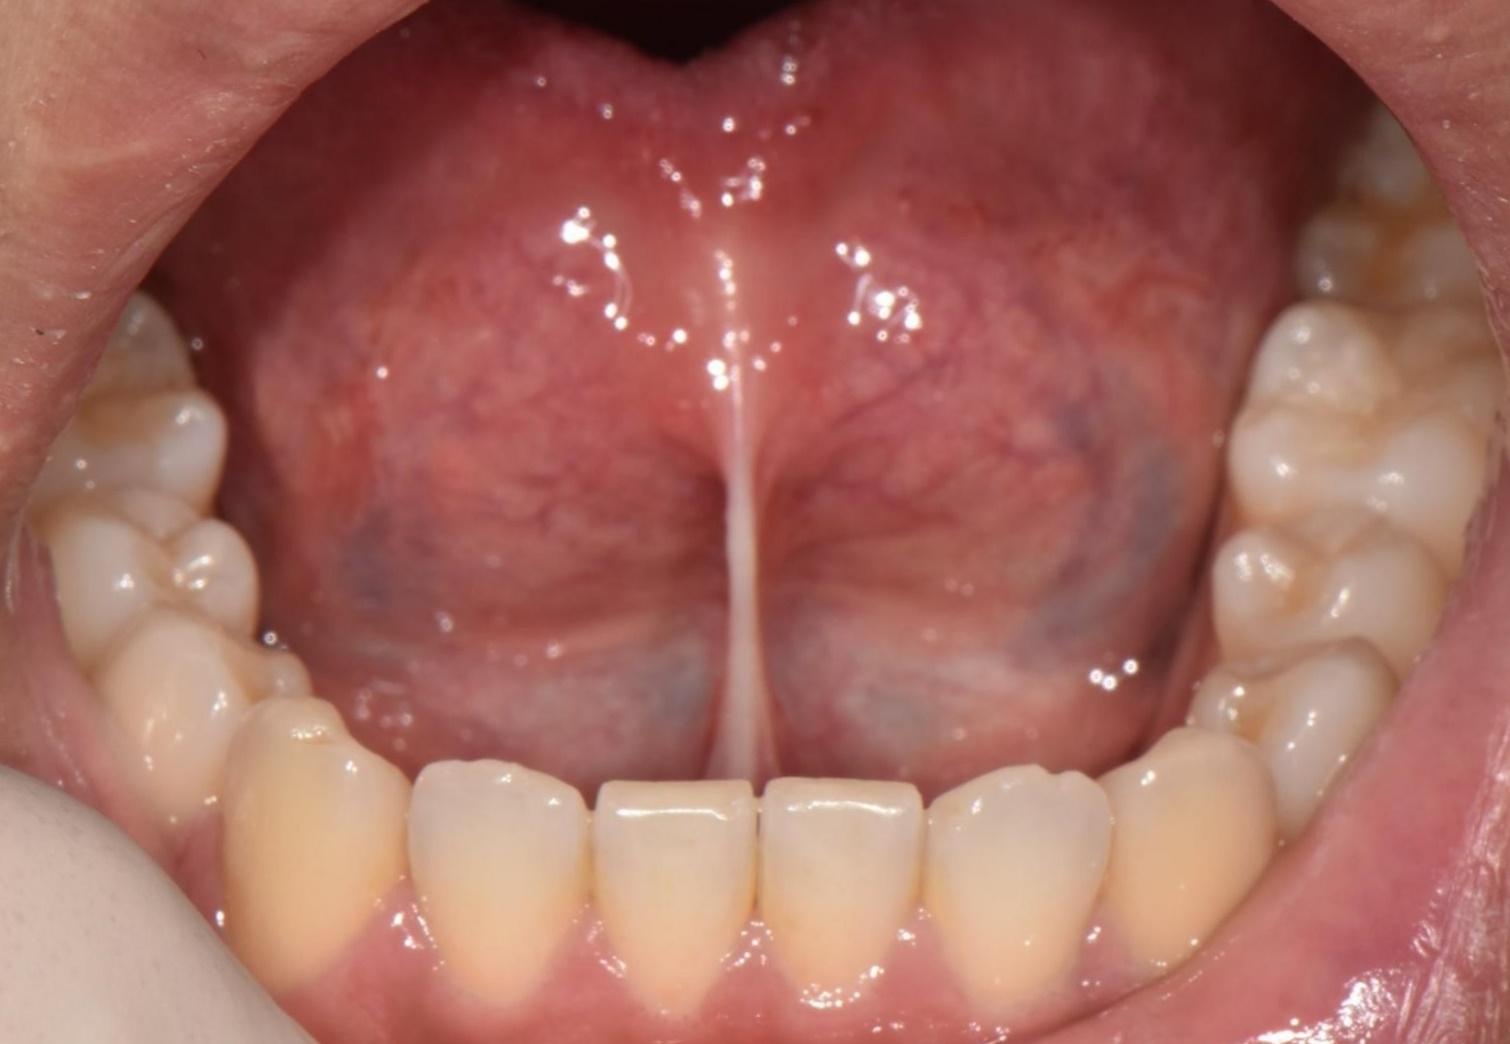

설소대절제술

전후사진

수술 전

수술 후